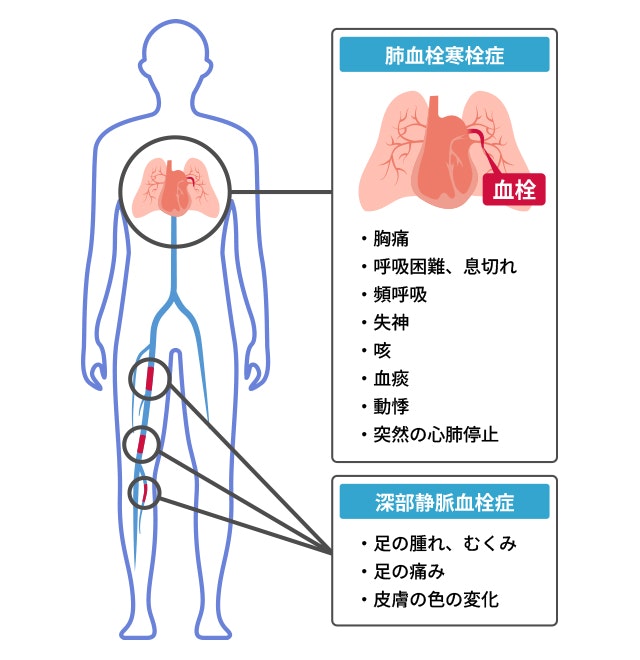

エコノミークラス症候群のイラスト素材29373435- PIXTA。

深部静脈血栓症イラスト - No: 24599005無料イラスト・フリー素材なら「イラストAC」。

川崎 静脈血栓塞栓症浅田内科・循環器内エコノミークラス症候群。

エコノミークラス症候群広島の調剤薬局 FINE PLUS まえだ薬局・プラス薬局 のブログ。

4 エコノミークラス症候群 肺血栓塞栓症 に関するQ&A - 4 エコノミークラス症候群 肺血栓塞栓症 に関するQ&A -災害時の対応について一般社団法人日本呼吸器学会。

エコノミークラス症候群病気と治療の検索サイト「メディカルブレイン」。

エコノミークラス症候群震災時に起こりやすい健康問題と予防法 1看護roo! カンゴルー。

上皇后さまが発症された深部静脈血栓症について解説します下肢静脈瘤の原因・症状・治療方法・予防方法などを専門医が解説。

4 エコノミークラス症候群 肺血栓塞栓症 に関するQ&A - 4 エコノミークラス症候群 肺血栓塞栓症 に関するQ&A -災害時の対応について一般社団法人日本呼吸器学会。

4 エコノミークラス症候群 肺血栓塞栓症 に関するQ&A - 4 エコノミークラス症候群 肺血栓塞栓症 に関するQ&A -災害時の対応について一般社団法人日本呼吸器学会。

静脈血栓塞栓症ではどのような症状がありますか? 静脈血栓塞栓症。